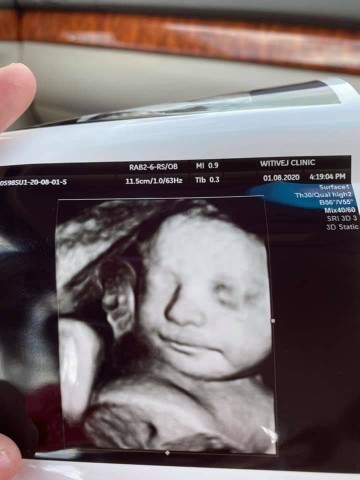

มาอวดรูปตอนซาวด์กันหน่อยค่ะ แม่ๆกำหนดคลอดเดือนไหนบ้างคะ